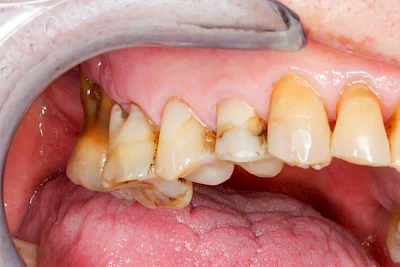

Gingivitis & Parodontitis: Stadien

Ist zunächst nur das Zahnfleisch von der Entzündung betroffen, spricht man von Gingivitis. Später, wenn auch der Knochen um die Zähne herum entzündet ist, spricht man von einer Parodontitis. Bei der Parodontitis wird der Knochen nach und nach abgebaut und das Zahnfleisch zieht sich zurück. Die Zahnhälse und Zahnwurzeloberflächen liegen mehr und mehr frei. Die Zähne werden zunehmend lockerer und fallen schließlich aus.